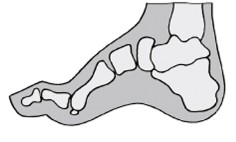

- Arco longitudinale rinforzato, accorciato, attivo e passivo, non correggibile

- Arco trasversale allargato, in molti casi appiattito, più basso del retropiede (metatarso cavo)

- Callosità nella zona dei metatasi e retropiede con sovraccarico dell’avampiede

- Piede equino e tendenza al varo dei retropiedi con possibile caduta laterale

-Dita ad artiglio contratte con calli sopra le articolazioni mediali